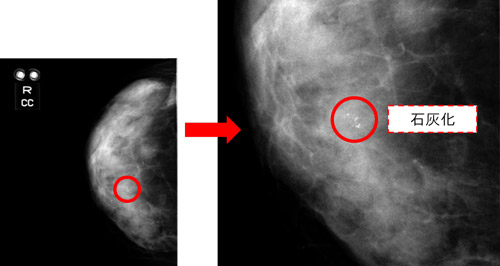

マンモグラフィーは、少ない放射線量で安全に乳がんの検出が可能な乳房専用のエックス線検査です。

撮影時は、がんと正常部分の区別がつきやすい画像にするため、圧迫板で乳房をはさみ、薄く伸ばして撮影します。